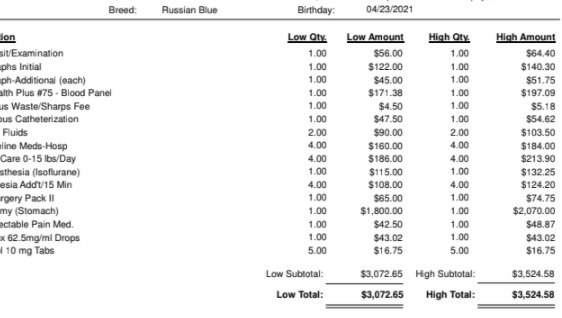

Luna's operation is going to cost anywhere between $3,072.65 and $3,524.58 (itemized list attached in photos), an unprecedented expense which I cannot afford in full at the moment. I will be exploring payment options with my Vet including care credit (which I do not expect to be approved for given I am only just establishing my credit).